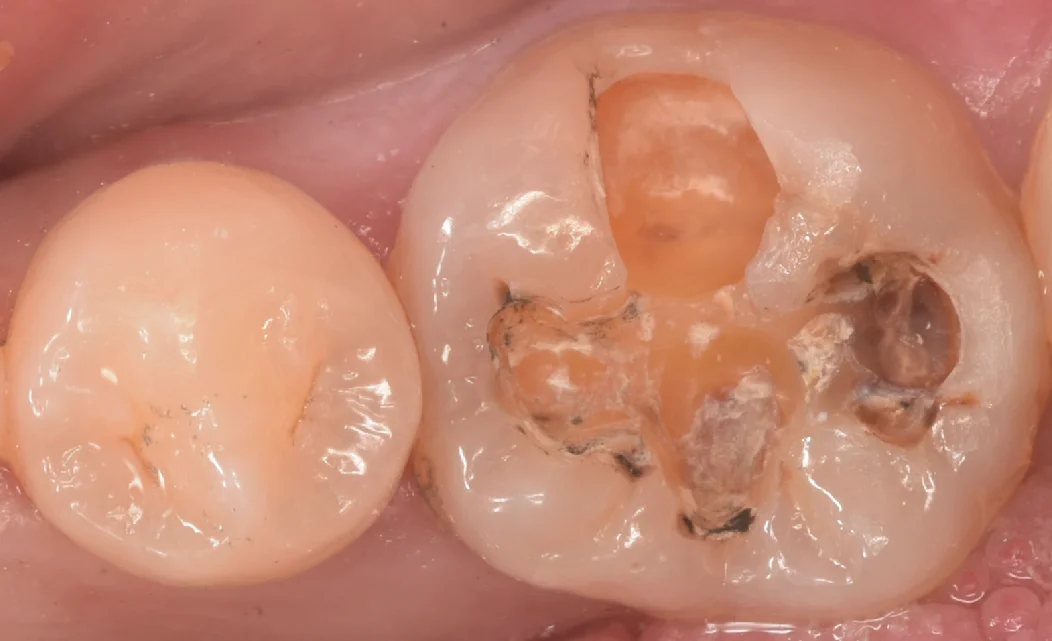

まずは術前からです。

今回は画面右側の保険の金属が入っている歯を治療していきます。

保険の金属の脇に隙間ができて、そこから虫歯が入り込んでいるのが画像上でもわかりますね。

金属を除去して内部のセメントを粗方とって虫歯を見やすくしたのがこちらになります。

非常にわかりづらいですが、画面上で上側の色が黄色っぽいところも全て虫歯になっている状態です。

臨床上で良く経験しますが、レントゲン上でそこまで大きくなくてもインレーを除去するとこのように内部で爆発的に虫歯が進行しているケースが多々あります。

そして虫歯を取り切ったのがこちらになります。

歯の色が綺麗に出たのがわかるかと思います。

全体的にほぼ同じような色になっていますよね。